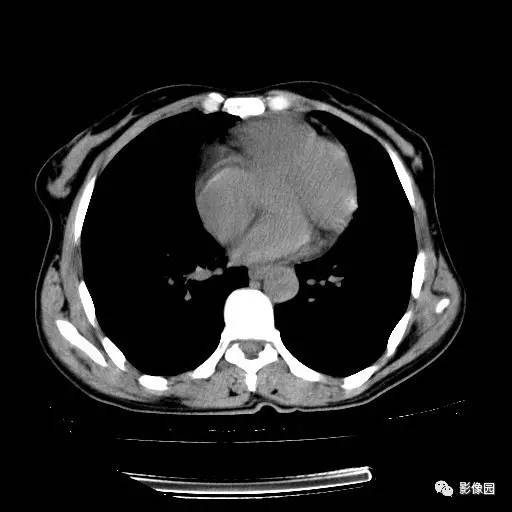

右肺下叶鳞癌1例CT

女,52岁,体检胸片发现右肺下叶小结节,患者无咳嗽、咳痰及咯血等症状。患者不同意增强检查。 医学百科网 | YxBaike.Com

手术后病理结果:(右肺下叶)鳞癌。 医学百科网 | YxBaike.Com